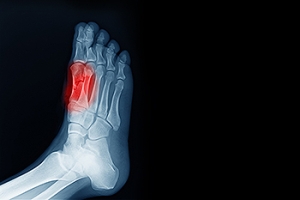

In most cases, foot surgery is often chosen as the last available option for conditions that have otherwise been unsuccessfully treated. Surgery may be necessary for several reasons, including the removal of foot deformities (e.g. bone spurs or bunions), arthritis problems, reconstruction due to injury, and congenital malformations (e.g. club foot or flat feet). Regardless of one’s age, foot surgery may be the only successful option for treatment for certain conditions.

The type of surgery one undergoes depends on the type of foot condition the patient has. For the removal of a bunion growth, a bunionectomy is necessary. If the bones in the feet need to be realigned or fused together, a surgical fusion of the foot is needed. For pain or nerve issues, a patient may require surgery in which the tissues surrounding the painful nerve are removed. Initially, less invasive treatments are generally attempted; surgery is often the last measure taken if other treatments are unsuccessful.

While in many cases surgery is often deemed as the final resort, choosing surgery comes with certain benefits. The associated pain experienced in relation to the particular condition is often relieved with surgery, allowing patients to quickly resume daily activities. The greatest benefit, however, is that surgery generally eliminates the problem immediately.

Podiatry history has shown that foot treatments continue to evolve over time. In the field of foot surgery, endoscopic surgery is just one of the many advanced forms of surgery. As technology vastly improves so too will the various techniques in foot surgery, which already require smaller and smaller incisions with the use of better and more efficient tools. Thanks to such innovations, surgery is no longer as invasive as it was in the past, allowing for faster and easier recoveries.